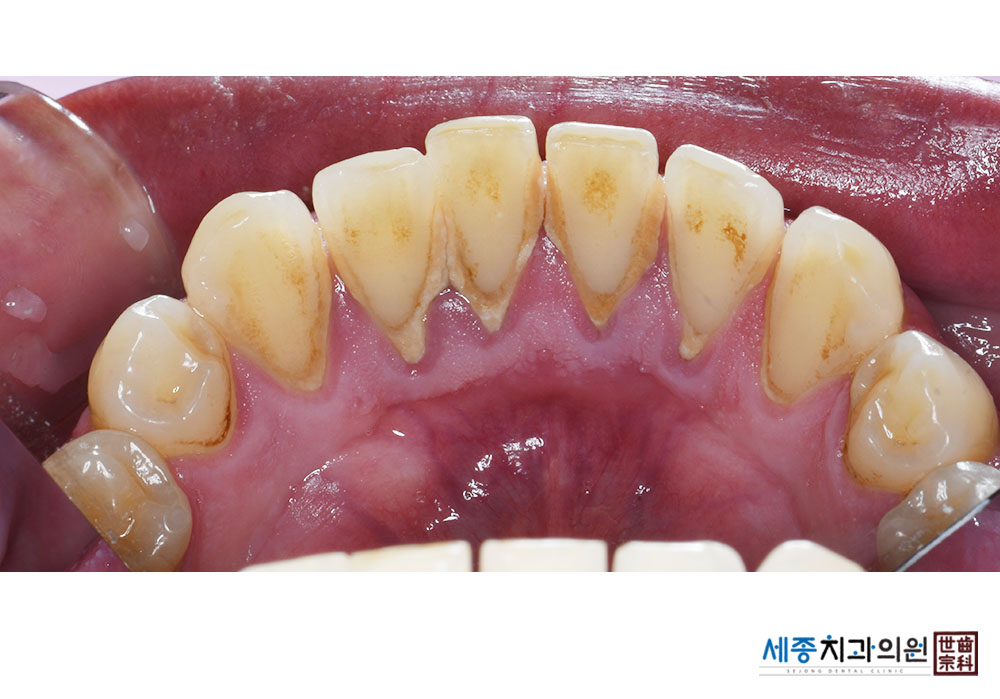

[스케일링] 치주질환 예방 스케일링

치료전 : 2022-08-31

치료후 : 2022-08-31

가글마취&저주파 스켈러를 사용한 스케일링